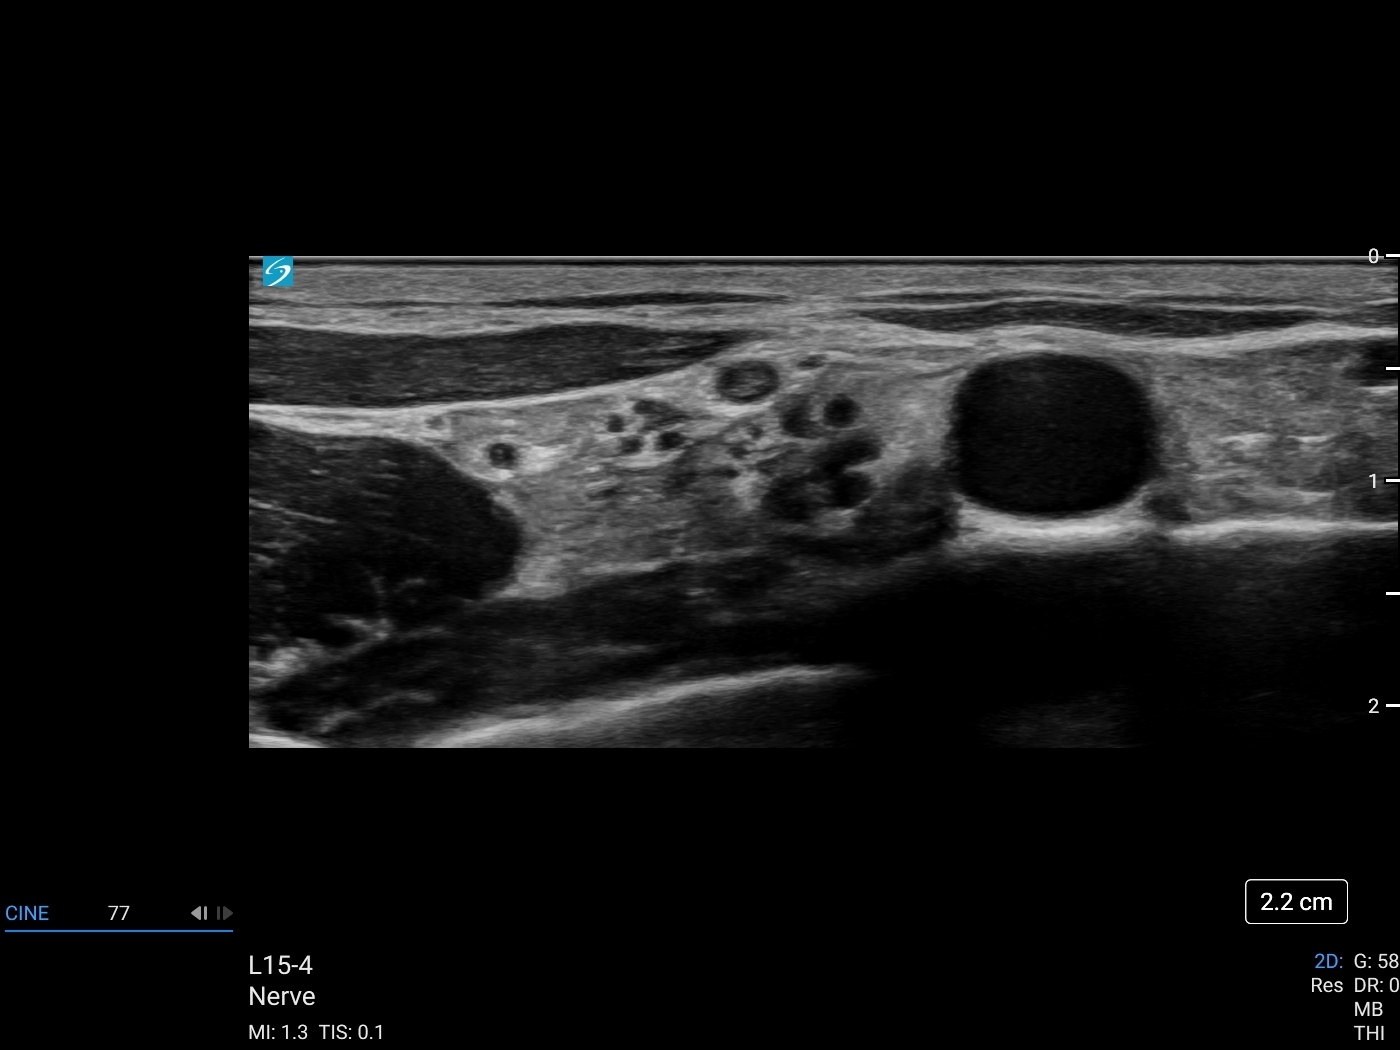

Spread of local anaesthetic surrounding the brachial plexus lateral to the subclavian artery and superior to the 1st rib.

• The brachial plexus is located lateral to the subclavian artery and superior to the first rib.

• Ideal ultrasound image of the supraclavicular brachial plexus should include: First rib, subclavian artery, and pleura. A clear delineation between the artery and brachial plexus should be visualised.